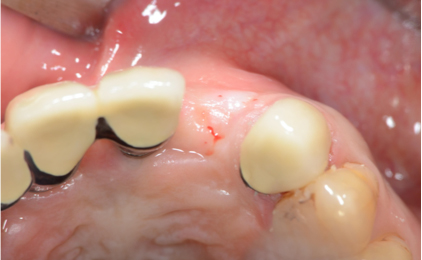

初診時口腔内写真

右下奥歯はブリッジが破損・脱離していました。歯のすり減りが激しく、歯ぎしりや食いしばりといった力の問題で歯を失ってきたことが予想される口腔内でした。

オペ時の写真

オペ時の写真になります。周囲骨を破壊しないよう、慎重に抜歯を行いました。かなり縁下までカリエスが進行していることがわかります。

サージカルガイドを使用し、3次元的位置関係を確認しながら、ドリリングならびに埋入を行いましたが、残念ながら、十分な初期固定は得られず、当初の計画を2回法へと変更しました。

右下奥歯はブリッジが破損・脱離していました。歯のすり減りが激しく、歯ぎしりや食いしばりといった力の問題で歯を失ってきたことが予想される口腔内でした。

右下奥歯はブリッジが破損・脱離していました。歯のすり減りが激しく、歯ぎしりや食いしばりといった力の問題で歯を失ってきたことが予想される口腔内でした。

オペ時の写真になります。周囲骨を破壊しないよう、慎重に抜歯を行いました。かなり縁下までカリエスが進行していることがわかります。

サージカルガイドを使用し、3次元的位置関係を確認しながら、ドリリングならびに埋入を行いましたが、残念ながら、十分な初期固定は得られず、当初の計画を2回法へと変更しました。

オペ時の写真になります。周囲骨を破壊しないよう、慎重に抜歯を行いました。かなり縁下までカリエスが進行していることがわかります。

サージカルガイドを使用し、3次元的位置関係を確認しながら、ドリリングならびに埋入を行いましたが、残念ながら、十分な初期固定は得られず、当初の計画を2回法へと変更しました。